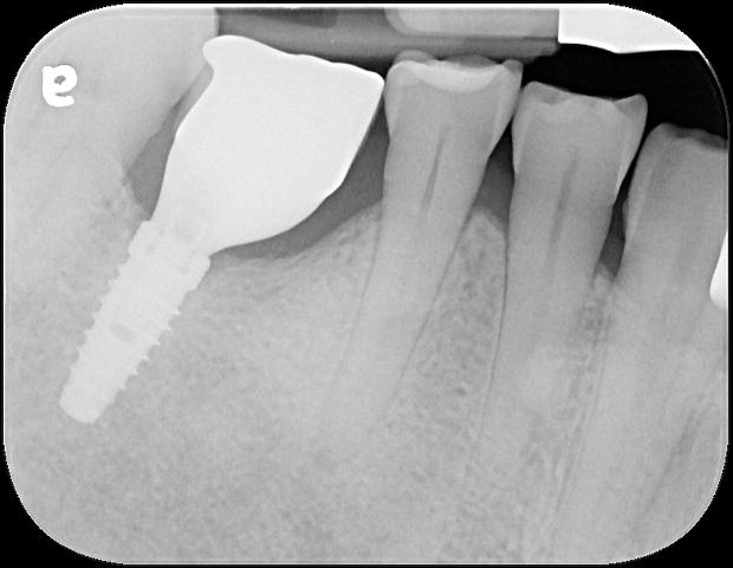

治療後口內照

患者的咀嚼機能逐漸恢復正常

透過牙冠修復受損結構,患者逐漸適應